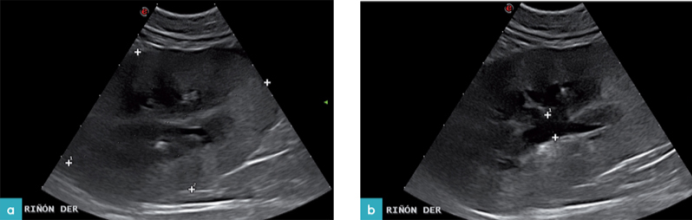

皮质回声增强是肾功能不全过程中最常见的发现,尽管其不是一种非特异性病变。引发出现该影像的另一个原因是急性肾损伤,同时通常还伴有肾肿大,腹膜后积液的情况 (图6和7.视频 3)。在老年猫中,输尿管梗阻提示存在急性肾损伤。急性肾损伤初步的影像是皮质回声增强,但是仍能看到皮质延髓区域的变化。随着疾病的进程,髓质回声提高,进而发展成为难以区分内部生理结构的状态。